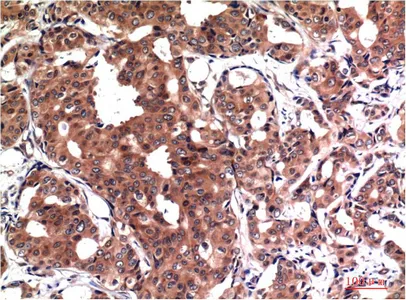

GSK3 beta Mouse Monoclonal Antibody

Cat: AMM03710

GSK3 beta (9F9) Mouse Monoclonal Antibody

Cat: AMM03603

GSK3 beta (9B1) Mouse Monoclonal Antibody

Cat: AMM03604

GSK3 beta (4C4) Mouse Monoclonal Antibody

Cat: AMM03605